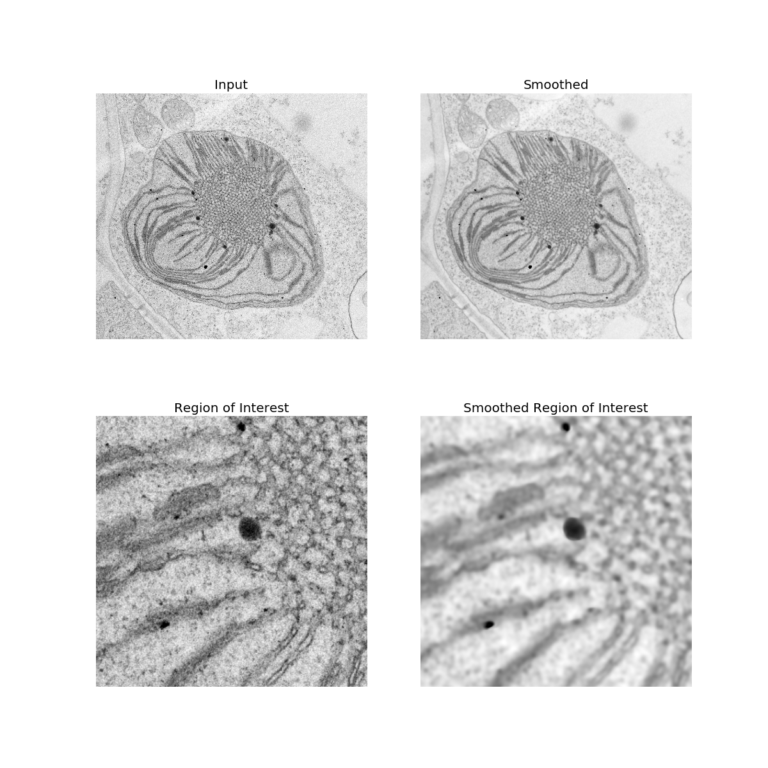

Edgepreserving Image Smoothing in Python Median Filter Edge Preserving Median filtering is a corner stone of medical image processing and it is extensively used in. — the median filter's selective noise reduction allows it to maintain sharp image edges, contours, and critical features, making it ideal for applications where preserving structural information is vital. — open access. Median Filter Edge Preserving.